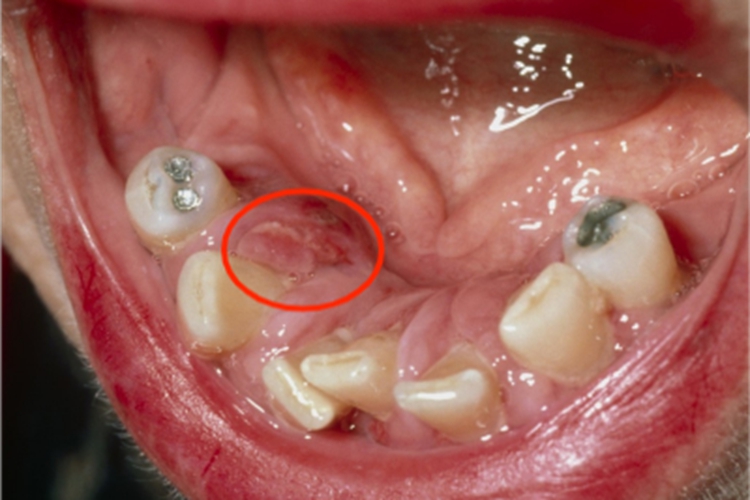

急性坏死性龈口炎多见于儿童,早期牙龈边缘及龈乳头红肿,以后迅速坏死,形成溃疡面,表面覆盖假膜,周围黏膜充血、水肿,患处牙龈易出血,疼痛明显,口内有特殊的坏死性口臭。